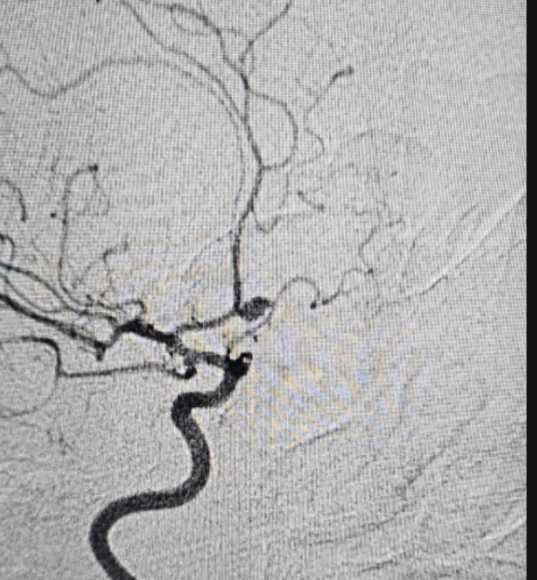

– Chụp cắt lớp vi tính mạch máu não.

– Chụp MRI/MRA.

– Chụp DSA mạch não.

– Can thiệp nội mạch (đặt coil, stent).

– Phẫu thuật kẹp cổ túi phình.